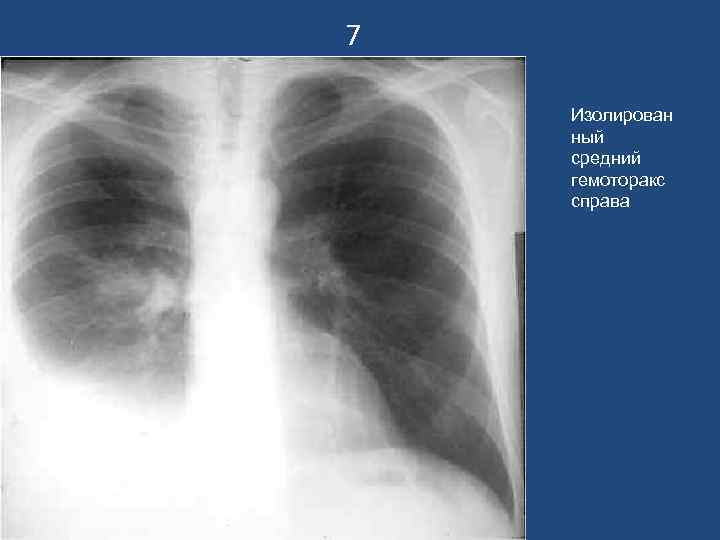

7 Изолирован ный средний гемоторакс справа